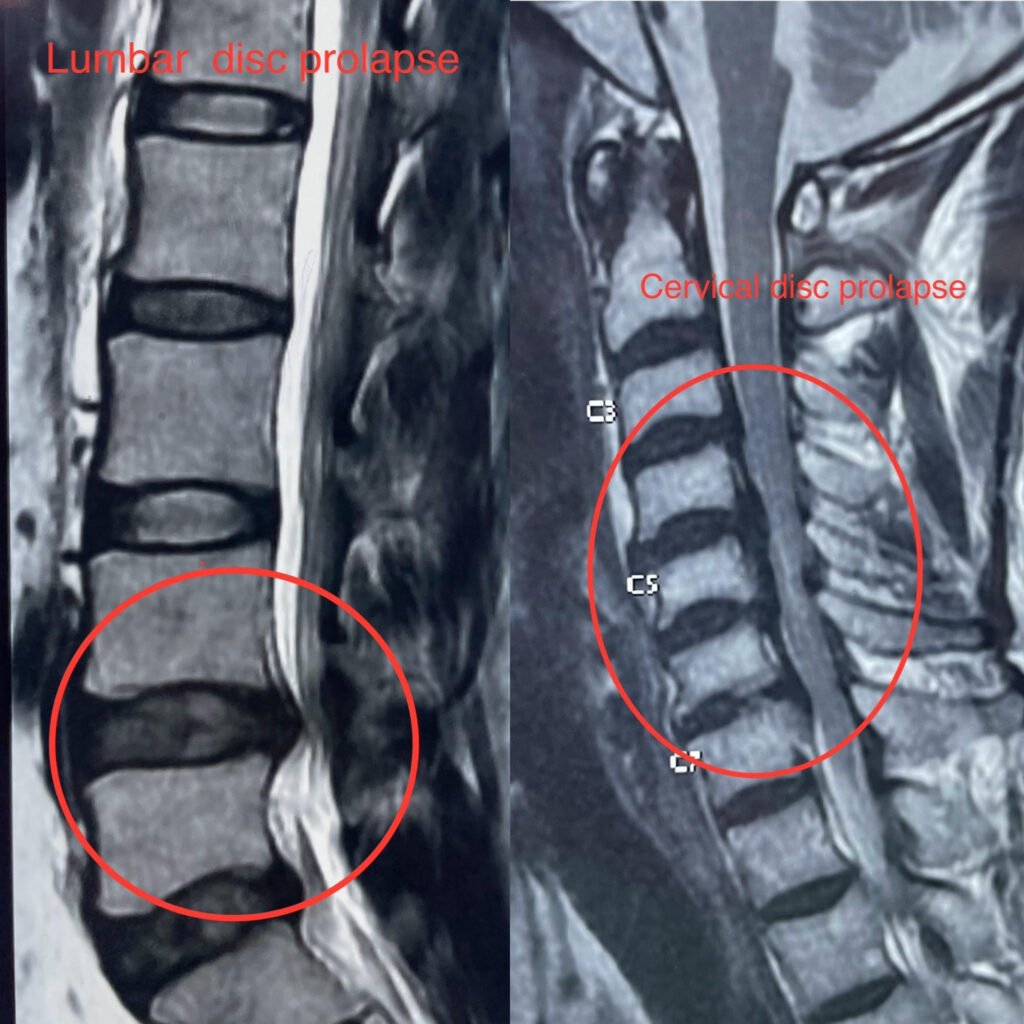

Disc Prolapse, also known as a herniated disc or slipped disc, occurs when the soft inner core of a spinal disc protrudes through the tough outer layer. This can irritate nearby nerves and cause pain, numbness, or weakness in the affected area.

• Diagnosis typically involves a physical examination, medical history, and imaging studies such as X-rays, CT scans, or MRI.